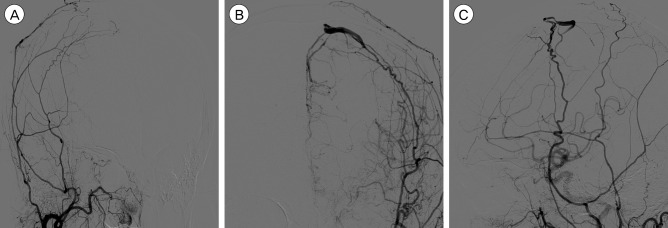

我们报告了一例硬脑膜动静脉瘘(DAVF)病例,在四个月的随访期间,患者的静脉引流模式自发地从 Borden II 型转变为 III 型。入院时,患者的神经系统状况恶化,并出现新的癫痫发作。入院后,使用 Onyx® 通过脑膜中动脉进行了血管内栓塞治疗。血管造影证实硬脑膜动静脉分流完全阻塞,患者的临床症状有所改善。虽然大多数硬脑膜动静脉瘘病例的临床过程和转归模式都是良性的,但仍需密切随访,以发现潜在的恶化。

We report a case of dural arteriovenous fistula (DAVF) that showed spontaneous conversion of venous drainage pattern from Borden type II to type III within a four month period of follow-up. Upon admission, the patient presented with aggravated neurologic status and newly developed seizure. After admission, endovascular embolization was performed through the middle meningeal artery with Onyx®. Complete obliteration of dural arteriovenous shunt was confirmed by angiography, and the patient's clinical symptoms improved. Although most cases of DAVF show benign clinical course and conversion pattern, close follow-up is required to detect potential aggravation.